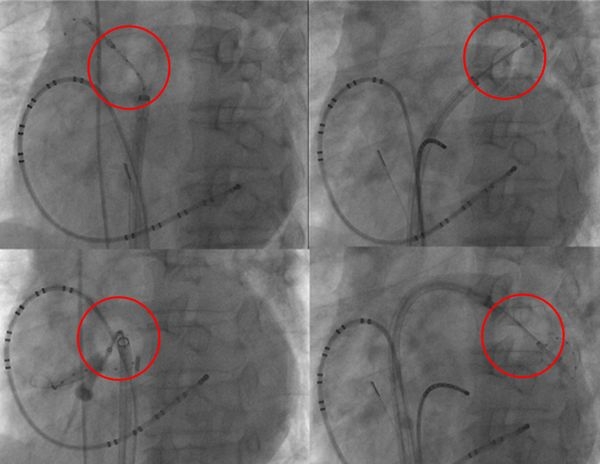

냉각 도자 절제술은 폐정맥 입구를 풍선으로 막은 후 폐정맥 입구전체를 영하 6~60도로 얼려 조직을 괴사시키는 시술이다.

냉각 도자 절제술은 기존 치료법인 고주파 도자 절제술과 효과는 비슷하면서도 시술 시간은 2시간 이내로 절반 이상의 시간을 단축시킨 것이 큰 장점이다. 건국대병원 부정맥 클리닉 권창희 교수는 “고주파도자 절제술은 폐정맥 입구 조직을 한 점, 한 점 괴사시켜나가는 방식으로 시간이 오래 걸리는 반면 냉각도자절제술은 냉각 풍선을 폐정맥 입구 전체에 밀착시켜 한 번에 냉각시켜 괴사시키기 때문에 시술 시간을 단축할 수 있다”고 설명했다.